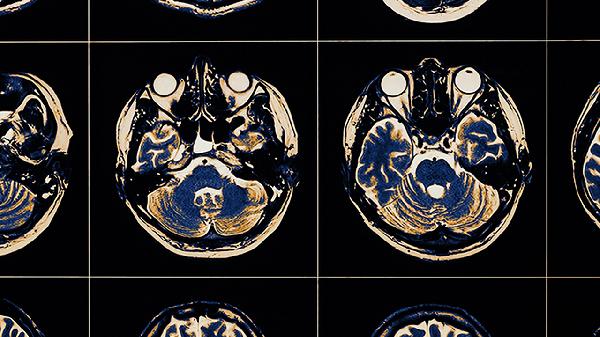

2、診斷方法:為了準(zhǔn)確評(píng)估結(jié)節(jié)的性質(zhì),醫(yī)生通常會(huì)建議進(jìn)行一系列檢查。這些檢查包括胸部X線(xiàn)、CT掃描、MRI成像以及纖維支氣管鏡取樣活檢。這些方法能夠幫助醫(yī)生了解結(jié)節(jié)的具體情況,從而做出準(zhǔn)確的診斷。